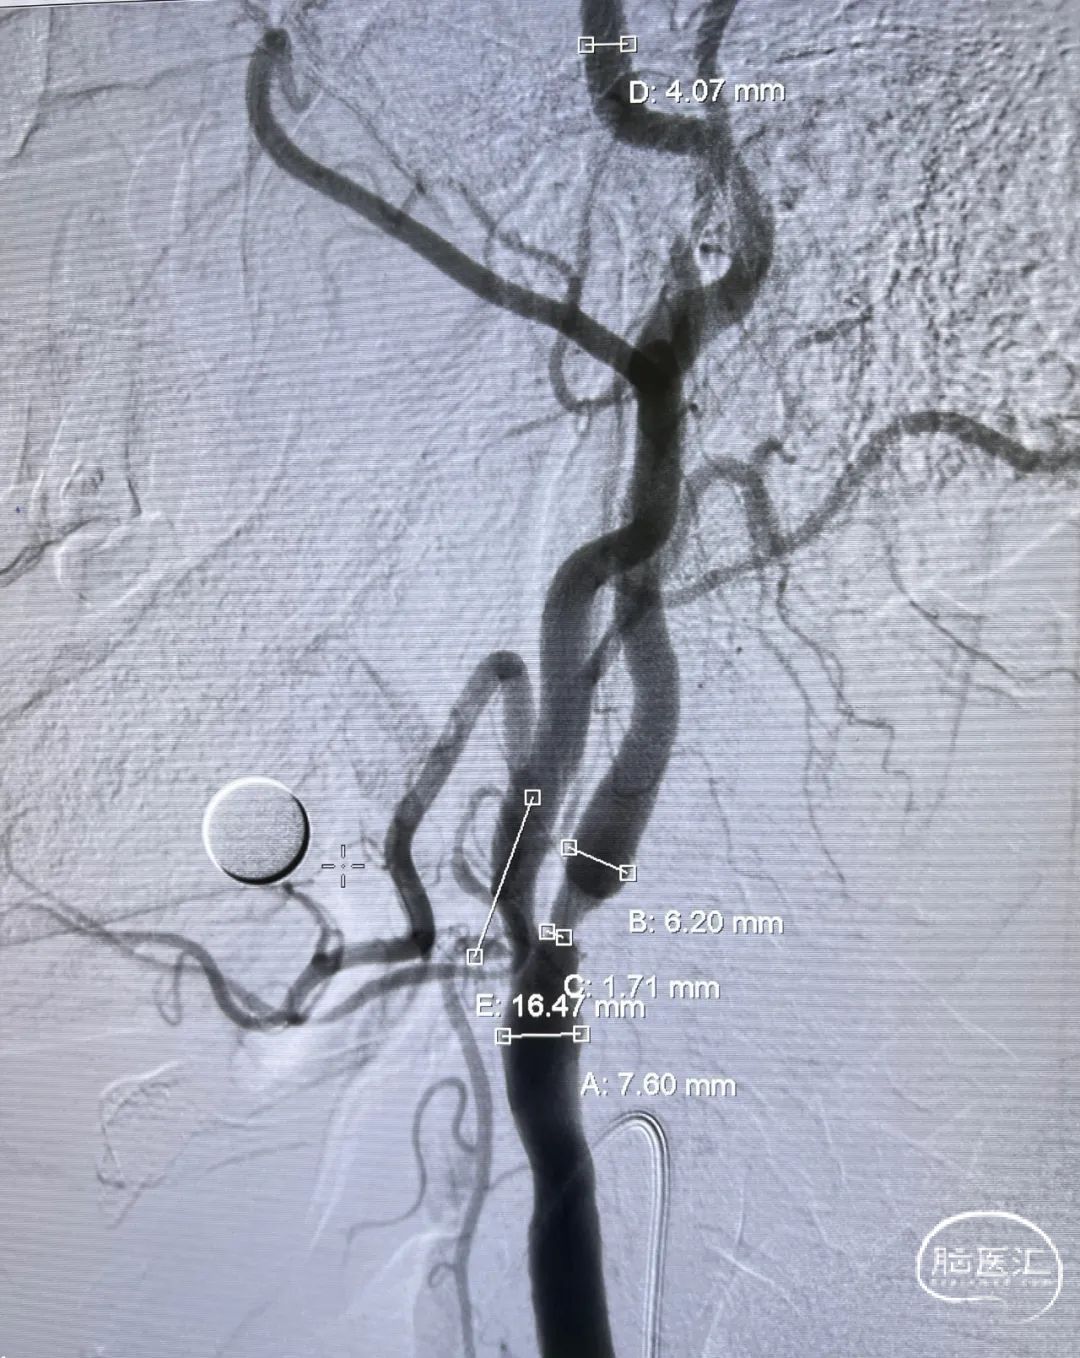

狭窄测量:

狭窄程度:75%,狭窄长度:16mm

狭窄近端参考血管直径:7.60mm

狭窄远端参考血管直径:6.20 mm